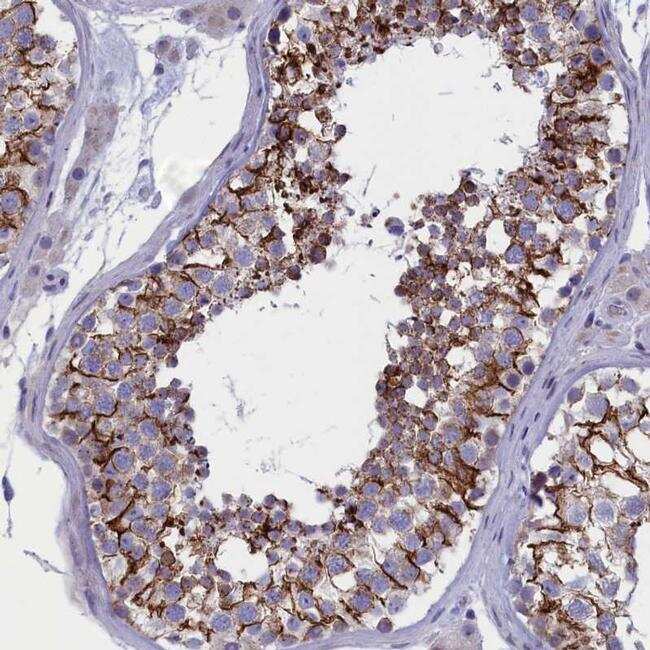

- Immunohistochemical analysis of FAM129C in human testis using FAM129C Polyclonal Antibody (Product # PA5-60306) shows strong cytoplasmic and membranous positivity in cells in seminiferus ducts.